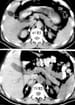

Computed tomography (CT) scans of the abdomen show normal adrenal glands several months before the onset of hemorrhage (upper panel) and enlarged adrenals 2 weeks after an acute episode of bilateral adrenal hemorrhage (lower panel). The attenuation of the adrenal glands, indicated by arrows, is increased after the acute event. Reproduced from Rao RH, Vagnucci AH, Amico JA: Bilateral massive adrenal hemorrhage: early recognition and treatment. Ann Intern Med. Feb 1 1989;110(3):227-35 with permission from the journal.